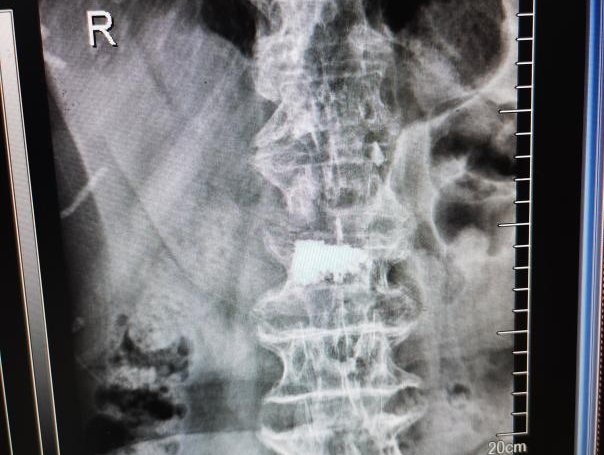

4月23日,贵州航天医院第58次晨读会由我院骨科副主任医师张艳金作学术交流,他以“加速康复指导下的快速手术”为题,详细讲解了老年股骨粗隆间骨折与儿童四肢骨折的临床诊疗难点,结合加速康复外科(ERAS)核心理念,重点阐述了ERAS理念在两大人群中的创新实践,实现患者入院后6至24小时内即可接受手术治疗。针对老年髋部骨折患者,提出通过多学科协作(MDT)与微创手术优化围术期管理,在确保安全前提下缩短术前等待时间,实施精准化麻醉及术后康复方案,可有效降低并发症发生率、改善患者生活质量和预后效果。在儿童骨折领域,强调微创术式与心理干预并行的双轨策略,既减少手术创伤对骨骼发育的影响,同时关注患儿心理疏导,实现生理功能与心理健康同步康复。并通过典型案例的影像学资料与随访数据,直观展示了ERAS理念指导下骨科治疗模式的创新成果。 贵州航天医院骨科 专家简介 赵学平 中共党员,骨科党支部书记、主任,主任医师 临床擅长:从事骨科临床工作30余年,对骨科常见疾病的诊治具有丰富的临床经验。 世界中医药联合会脊柱康复专业委员会常务理事,中华中医药学会整脊分会常务委员,中国中西医结合学会骨伤科分会肢体矫形功能重建与康复专家委员会常务委员,中国研究性医院学会骨科创新与转换专业委员会关节外科学组保髋工作委员会常委,中国康复技术转化及发展促进会骨外科与康复技术转化专业委员会常务委员,泛珠三角区域运动医学联盟(PPRD-SMA)理事会常务理事,中国研究型医院学会运动医学专业委员会委员,贵州省中医药学会整脊分会副主任委员,贵州省中西医结合学会银质针专业委员会副主任委员,贵州省康复医学会骨与关节专业委员会常务委员,贵州省人民医院骨科专科联盟常务理事,贵州省康复医学会骨内科专业委员会常务委员,中华医学会贵州省骨科学会委员,贵州省康复医学会脊柱脊髓专业委员会常务委员,贵州省运动医学分会委员,贵州省康复医学会骨与软组织肿瘤专业委员会委员,遵义市医学会创伤分会副主任委员,贵州省康复医学会骨内科专业委员会遵义地区分会常务委员,遵义市医疗事故鉴定、伤残鉴定、工伤鉴定、司法鉴定专家。 长期从事骨科临床研究及教学工作,在国家级、省部级杂志发表论文20余篇,SCI论文2篇,参与主编骨科专著2部,主持省部级科研项目2项,参与指导省部级、市级科研项目6项。 陈明勇 骨科副主任,副主任医师 临床擅长:从事创伤骨科工作约20年,对骨缺损、骨不连、骨肿瘤、肢体畸形等的肢体矫形重建及功能重建,慢性化脓性骨髓炎的根治治疗、糖尿病足的保肢治疗、快速康复理念(ERAS)下的老年骨折的诊治,四肢复杂骨折的诊治,四肢骨折等微创手术治疗具有丰富的临床经验。 2004年毕业于遵义医学院临床专业,曾在中国人民解放军总医院、广西医科大学第一附属医院、上海第六人民医院骨科进修。中国中西医结合学会骨伤科专业委员会横向骨搬移治疗糖尿病足及微血管网再生学组首届委员,遵义市医学会创伤分会常务委员。 瞿 辉 中共党员,骨科副主任医师 临床擅长:对骨科的常见病、关节外科、脊柱外科及运动医学疾病的诊治具有丰富的临床经验,熟练掌握骨科手术操作技术。 毕业于遵义医学院临床医学系,2005年前往广州中山大学第一附院骨显微医学部进修学习,2011年前往成都华西医院进修学习,并多次在省内外学习骨科相关知识,是中华医学会骨科分会会员。 赵兴东 骨科主任医师 临床擅长:擅长骨科的常见病及各种创伤、四肢骨折创伤修复、骨感染、手足疾病的诊治和手足体表畸形的矫形整复,熟练掌握骨科四肢骨病及创伤的手术操作技术,尤其在四肢关节复杂性损伤、手足外伤、组织缺损创面、难治创面的皮瓣修复方面及平足、高弓足矫形方面及四肢慢性疼痛诊治、康复方面具有丰富的临床经验。 硕士研究生,毕业于遵义医学院临床外科系,2015年前往山东省立医院手足外科进修学习;遵义市医学分会创伤分会第一、二届委员,遵义市手外科医学会第二委届员会常务委员;在省级及省级以上期刊发表文章9篇,参编著作2部,参与主持并完成市级课题1项,参与市级课题2项、省级课题1项。 张艳金 中共党员,骨科副主任医师 临床擅长:从事骨外科工作16年,对复合伤、多发伤的救治、四肢骨干骨折、关节周围骨折、骨肿瘤、骨髓炎等诊治具有丰富的临床经验。 中共党员,硕士研究生,2006年本科毕业于山西医科大学第二临床医学院,2011年研究生毕业于北京军区总医院;在“老年COPD患者合并髋部骨折的诊治”国际合作课题组研究两年,在老年髋部骨折的诊治方面具有丰富的经验,并发表论文6篇;主持遵义市级课题1项,承担遵义医科大学的临床教学工作,获得遵义医科大学优秀带教老师荣誉。编撰有《骨科疾病诊疗精粹》一书,开展2项新技术,编撰地方规范《务川自治县创伤骨科常见疾病诊疗规范》一书。 张俊凯 骨科副主任医师 临床擅长:从事骨科临床工作28年,对创伤骨折、骨感染、骨缺损、骨不连等外科诊治,四肢骨折的微创手术治疗,四肢复杂骨折(如关节内粉碎性骨折、多发骨折等)的损伤控制及手术治疗等具有丰富的临床经验。 1995年毕业于遵义医学院临床专业,2009年前往复旦大学附属医院骨科进修1年。 卢懿明 中共党员,骨科副主任医师 临床擅长:从事骨科工作18年,对创伤骨折、四肢骨折的微创手术治疗、四肢复杂骨折(如关节内粉碎性骨折、多发骨折等)的损伤控制及手术治疗,尤其是髋部骨折的PFNA等微创技术,踝关节骨折、膝关节周围骨折的Mipo微创技术等具有丰富的临床经验,开展了4项新技术,发明6项新型专利技术。 2005年毕业于遵义医学院临床专业,2017年,前往南方医科大学第三附属医院骨科进修半年,回院后运用Mipo技术对骨干骨折及干骺端骨折的治疗技术,同时积极开展骨盆骨折、髋臼骨折腹直肌外侧切口的应用;发表了多篇专业论文,经常参与省内外学术交流会授课,获得医院荣誉称号多个。 邬夏荣 骨科副主任医师 临床擅长:从事骨科工作16年,对四肢复杂骨折、骨肿瘤的诊治,尤其是足踝创伤、慢性踝关节损伤、平足症等诊疗具有丰富的临床经验。 2006年毕业于遵义医科大学临床医学专业,曾在陆军军医大学西南医院进修学习,发表多篇骨科学术论文。 余德怀 中共党员,骨科副主任医师 临床擅长:从事骨科工作10余年,对运动医学、骨关节、脊柱外科常见病、多发病的诊治具有丰富的临床经验。 硕士研究生,2011年毕业于遵义医学院临床医学专业,曾前往遵义医科大学附属医院运动医学专业进修学习;是贵州省医学会运动医学分会青年委员,西部关节镜联盟委员;发表多篇骨科学术论文。 冯 乾 骨科副主任医师 临床擅长:从事骨科工作近20年,熟练掌握骨科多发病及常见病的诊治,尤其对脊柱退变性疾病的诊断及治疗具有丰富的临床经验,主要研究脊柱微创相关治疗方式,能熟练开展椎间孔镜及UBE。 曾前往北京大学第三医院进修学习疼痛及椎间孔镜、首都医科大学友谊医院专业进修脊柱内镜;是贵州省康复医学会第三届脊柱脊髓专业委员会委员;发明专利3项、发表脊柱外科专业论文多篇。 赵小锋 中共党员,骨科副主任医师 临床擅长:从事骨科临床工作11年,对骨科常见病、多发病诊疗有较为丰富的临床经验,擅长脊柱相关疾病诊断及治疗,尤其是颈、腰、腿疼痛疾病诊断及治疗,擅长胸腰椎骨折微创经皮穿刺内固定术、经皮穿刺椎体成形术、经皮穿刺脊柱内镜下腰椎间盘摘除术、单纯开创腰椎间盘摘除术、腰椎滑脱复位椎间植骨椎融合内固定术、腰椎管狭窄减压融合内固定术及人工髋、膝关节置换术等。 2012年毕业于遵义医学院外科学专业硕士研究生,2019年参加“遵义市115医学人才精英计划”于上海交通大学第一附属医院培训学习,2023年于北京大学第三人民医院脊柱外科进修学习,曾获得遵义市优秀医师荣誉称号。 遵义市手外科第一届委员,遵义市医学会创伤分会第一届委员,遵义市医学会创伤分会第二届委员,贵州省康复医学会第三届脊柱脊髓专业会委员,遵义市医学会烧伤与整形外科学分会委员,发表论文5篇,其中国家级核心期刊1篇,SCI论文1篇,主持市级课题1项并结题,参与市级课题2项。 贵州航天医院骨科 简介 基本情况 贵州航天医院骨科组建于20世纪60年代,前身是以创伤和断肢(断指)再植闻名于世的上海市第六人民医院骨科,中国断肢(断指)再植的奠基者、中科院院士陈仲伟等著名专家、学者多次莅临科室指导医疗、教学,是贵州省最早拥有专业骨科技术科室之一,在70年代开展了贵州省首例断肢(断指)再植手术。组建50余年来,诊治患者已逾百万,挽救了无数的伤病员,成为了保障遵义地区人民群众健康的重要支撑。 经过几代人的不懈努力,今天的骨科,已由创伤骨科发展至骨病、骨肿瘤、骨结核等领域,现有脊柱外科、关节外科、四肢创伤、手足外科四个亚专科,成为了集医疗、教学、科研于一体的综合学科,是贵州省临床重点专科、遵义市临床重点专科、遵义市骨科临床医学中心、遵义市基层骨科专科联盟理事长单位。 科室目前开放床位110张,共有医护人员50余人,副高级以上专家18人,硕士研究生15人。拥有一流骨科医疗设备多台,每年不定期选派优秀技术骨干到全国各大知名医学院校进修、学习、参观、交流,并邀请国内、国外知名专家教授来院进行交流、指导,通过不断引进国内外先进的诊疗技术,科室医疗技术水平稳步提升,为广大人民群众提供了优质的医疗服务。 专科特色 骨一科 (一)骨缺损、骨不连的肢体与功能重建 胫骨横向骨搬移技术治疗糖尿病足: (二)慢性骨髓炎的根治治疗 (三)肢体缺血性疾病如糖尿病足、脉管炎的保肢治疗 (四)皮瓣修复 (五)复杂创伤的治疗 (六)老年髋部骨折及小儿骨折快速手术 老年髋部骨折: 骨二科 (一)胸腰椎骨折微创经皮椎弓根螺钉固定术 (二)老年性骨质疏松性患者腰椎滑脱脊柱内固定术(骨水泥螺钉) (三)V形双通道脊柱内镜技术(VBE)腰椎融合术治疗腰椎退行性疾病 (四)老年性骨质疏松性骨折(PVP/PKP)术 (五)人工髋关节置换术 (六)双侧股骨头坏死人工全髋关节置换 (七)右侧全髋置换术后假体周围骨折翻修 (八)人工膝关节置换术 (九)人工膝关节假体松动翻修 (十)关节镜技术 传统手术切口 关节镜技术切口 诊疗范围 骨一科 1.四肢创伤、矫形。 2.手、足踝外科。 骨二科 end